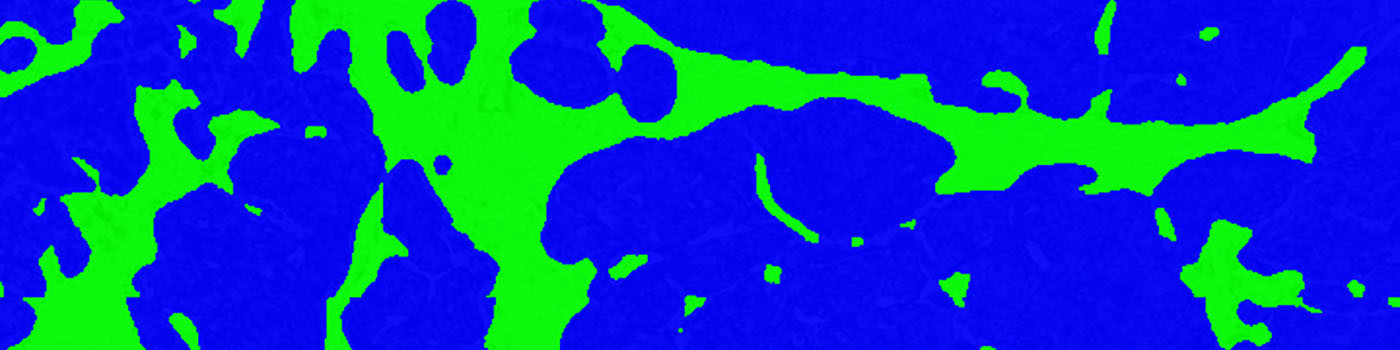

Figure 2

The same field of view as in FIGURE 1 after the initial automatic detection of the Tumor region (blue label) and Non-tumor region (green label).

Figure 3

The same field of view as in FIGURE 1 after the final automatic classification of Tumor region (blue label) and Non-tumor region (green label).

The classification of the tumor and non-tumor region is based on an intensity based thresholding classifier. The classifier segments the tissue into three parts: tumor, non-tumor and background corresponding to blue-, green- and clear-label, respectively.

The last processing step is the post-processing. Here the tumor-, non-tumor and clear-labels are expanded, thereby closing any clear-holes in the tumor- and non-tumor labels (See FIGURE 2 and 3).